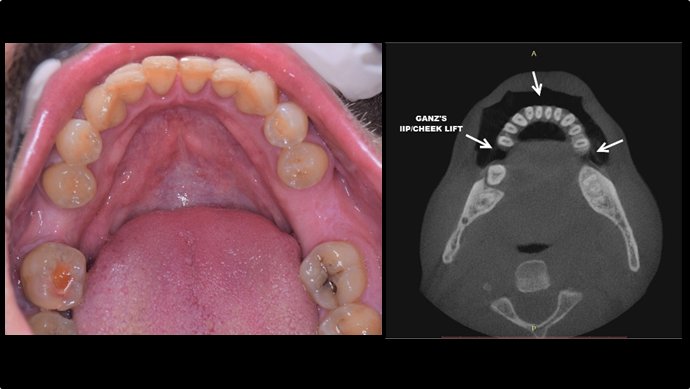

Clinical case: EImmediate implant placement & loading of #35 extraction socket with defect

- Courtesy of Dr. Kwang Bum Park, Korea -

“Automated customized drilling protocols for optimum implant stability/ ONE-DAY implants ”

Clinical case: : Immediate loading of lower molars using R2Gate prefabricated 3D-printed provisional restoration

- Courtesy of Dr. Sam Omar, Egypt -